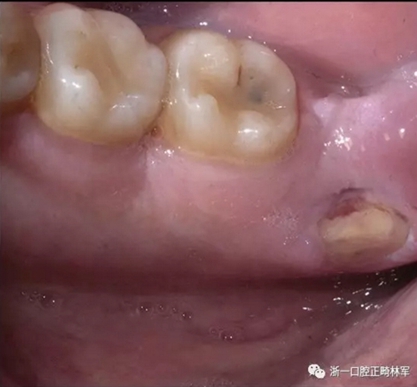

兩天后,患者自述覆蓋在下頜舌骨嵴的一塊粘膜脫落,暴露了下方的骨質(zhì)(圖4),伴有疼痛和燒灼感,特別是與某些食物(面包,辛辣食物)相關(guān)。 因此,他被轉(zhuǎn)診到了荷蘭阿姆斯特丹的學(xué)術(shù)醫(yī)學(xué)中心的口腔頜面外科治療舌側(cè)下頜骨骨壞死。

圖4. 右側(cè)下頜舌骨嵴區(qū)域的舌側(cè)下頜骨骨壞死